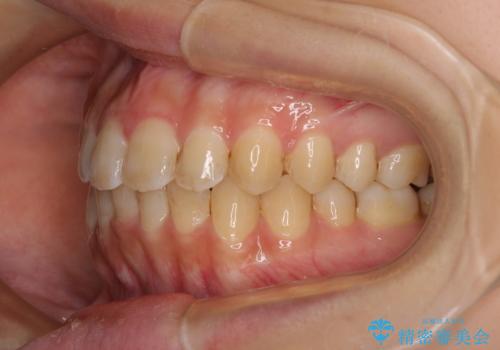

上顎歯列が前方にあり、口元が閉じにくくなっていたため、既に装着されている装置を使用して上顎歯列全体を後方に移動させていくこととしました。

舌の突出癖の影響か、なかなかスペースが閉じきらず、治療期間は予定よりも長期間となりました。

舌突出癖改善のトレーニングの重要性を認識することとなりました。